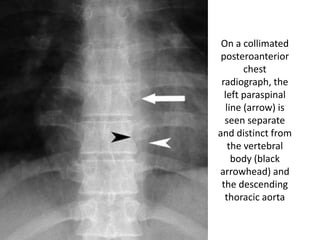

On a collimated

posteroanterior

chest

radiograph, the

left paraspinal

line (arrow) is

seen separate

and distinct from

the vertebral

body (black

arrowhead) and

the descending

thoracic aorta

CT scan shows the left paraspinal line. The descending aorta holds the pleural

On a collimated posteroanterior chest radiograph,the left paraspinal line (arrow) is seen separate and distinct from the vertebral body (black arrowhead) and the descending thoracic aorta